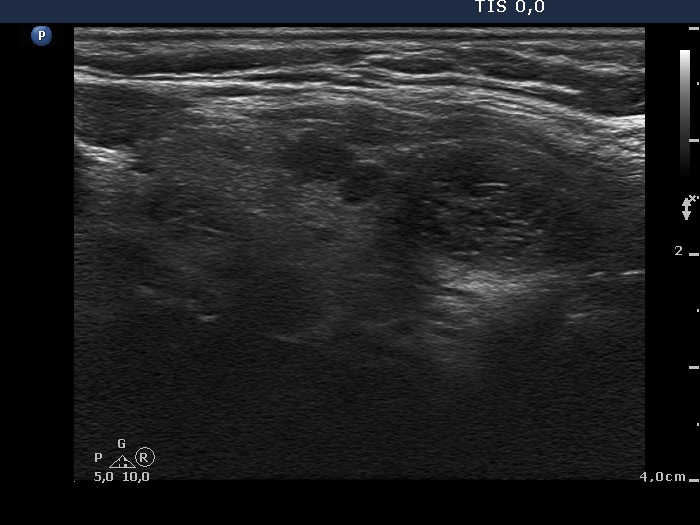

Benign hyperplastic nodules (histological diagnosis) - case cons 024 |

The larger lesion has a solitary bright figure which shape stands for a comet-tail artifact.

There are pale lines and granules within the nodule - these figures correspond to a connective tissue. The three granules are probably also presentations of a connective tissue.